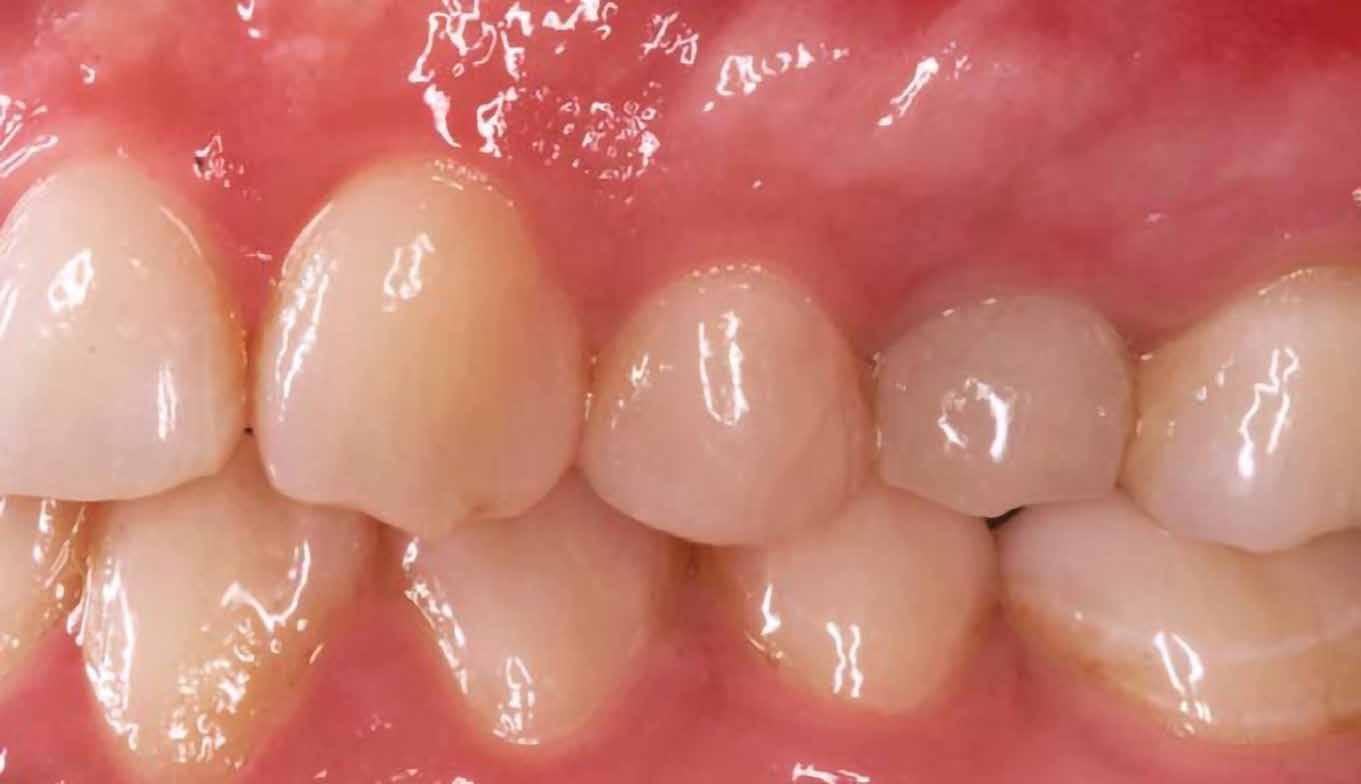

16. ábra: Klinikai kép az implantátumok körüli lágyszövetről a végleges pótlásátadás után. – 17. ábra: Klinikai kép az implantátumok körüli lágyszövetről egy évvel az átadást követően. – 18. ábra: Klinikai kép az implantátumok körüli lágyszövetről két évvel az átadást követően. – 19. ábra: Klinikai kép az implantátumok körüli lágyszövetről öt évvel az átadást követően.

A műtétet követően napi kétszeri, 0,12%-os klórhexidin tartalmú szájvízzel történő öblögetést javasoltunk a páciensnek, két héten keresztül. Gyulladáscsökkentésre 8 óránként 400 mg Ibuprofént javasoltunk, három napon keresztül. A páciens elmondása szerint sem fájdalmat, sem különösebb diszkomfortot nem tapasztalt. Ezt követően, további 4 héten keresztül, 0,2%-os klórhexidin tartalmú szájvízzel történő öblögetést javasoltunk a betegnek és instruáltuk, hogy lehetőleg ne mossa fogkefével az érintett területet. A varratokat egy héttel később távolítottuk el. A donor és a recipiens terület – 10 nappal a műtétet követően – kiválóan gyógyult (15–16. ábra). Az ezt követő kontrollokat a következő időpontokban ejtettük meg: kettő, illetve négy héttel a műtét után, majd három, hat és tizenkét hónappal később, ezt követően pedig félévente (17–20. ábra). Minden kontroll alkalmával professzionális fenntartó kezelést végeztünk a területen.

ságát egy ISO #15-ös endodonciai fájllal mértük 2 mm-re a marginális ínyszéltől meziálisan, disztálisan, illetve az implantátum tengelyében (mint referenciapont). A keratinizált íny szélességét parodontológiai szondával regisztráltuk a kiindulás és a kontrollvizsgálatok alatt. A méréseket elvégeztük a műtét előtt, közvetlenül utána, 4 héttel később, majd egy és két év elteltével. A klinikai paramétereket (keratinizált íny szélessége, lágyszövet volumen és recessziófedés) regisztráltunk a kiinduláskor és az utánkövetés időpontjai alatt. Kiinduláskor a feszes íny szélessége minimális volt (1 mm). A keratinizált ínyszélesség terén négy hétnél 2 mm-t sikerült nyerni, egy évnél 3 mm-t és öt év alatt 5 mm-t. A recessziót 100%-osan sikerült fedni 4 hét után, és ez nem változott sem egy év, sem öt év után.